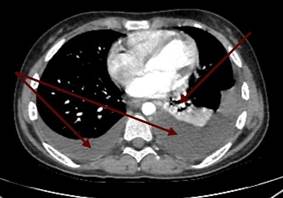

Было проведено лечение: инфузионная, антибактериальная (амклав, цефипим+сульбактам, амоксициллин), противогрибковая, обезболивающая, антигипертензивная, антисекреторная, эрадикационная, диуретическая, противорвотная, гемостатическая терапия. На фоне лечения состояние ребенка оставалось нестабильным, отмечалось неоднократное ухудшение – снижение сатурации кислорода до 86%, слабость, тошнота, периодически рвота, боли в животе опоясывающего характера с иррадиацией в поясницу, боли в паховой области, отсутствие аппетита, повышение артериального давления до 130/80 мм рт. ст. По решению телемедицинской консультации ребенок был переведен в ФГБУ «Национальный медицинский исследовательский центр онкологии им Н.Н. Блохина» Минздрава, где находился 9 дней. По данным ПЭТ КТ (позитронно-эмиссионной компьютерной томографии) с туморотропными РФП – выявлена опухолевая ткань с гиперметаболической активностью 18F-ФДГ в стенках тела желудка, множественных лимфатических узлах (выше и ниже диафрагмы), по плевре с обеих сторон. Плеврит. Асцит. Выставлен диагноз: «Перстневидноклеточный рак желудка с T3bN3bM1b, метастазы в регионарные, отдаленные лимфоузлы, кости таза. Стадия опухолевого процесса: IV». Была рекомендована полихимиотерапия по месту жительства в рамках клинических рекомендаций RUSSCO по схеме FOLFOX6 с оценкой динамики через 2 блока. В детской больнице был начат 1-й курс полихимиотерапии согласно протоколу FOLFOX 6 – оксалиплатин 85 мг/м2, лейковирин 400 мг/м2, 5-фторурацил 2000 мг/м2 с проведением сопроводительной терапии. После окончания первого курса сохранялось тяжелое состояние за счет диссеминации опухолевого процесса, выраженной интоксикации, хронического болевого синдрома, дыхательной недостаточности I степени на фоне двустороннего плеврита, асцита. Температура тела повысилась до фебрильных значений, присоединился кашель. Аускультативно в лёгких дыхание стало ослабленным в нижних отделах справа и слева, выслушивались разнокалиберные хрипы с двух сторон. На КТ органов грудной клетки (рис. 4) в плевральных полостях отмечалось большое количество неоднородного содержимого, в S4, S5 левого легкого – признаки инфильтративных изменений.

Рис. 4. Компьютерная томограмма органов грудной клетки пациентки с раком желудка: инфильтративные изменения верхней доли левого легкого, более вероятно, воспалительного генеза (1); картина двустороннего гидроторакса (2)